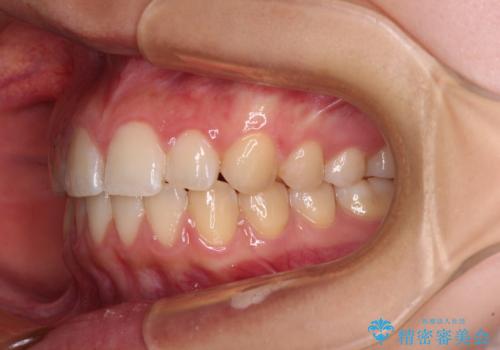

奥歯の咬み合わせを見ると、上顎が下顎に対して相対的に前方にあり、上下の前歯が接触していない状態でした。

咬み合わせを改善するためには、上顎臼歯を後方に移動させた咬み合わせにする必要があります。

インビザライン単体で改善することも可能ですが、咬合力が強く、単位で達成する可能性が低いと考えられたため、カリエール・ディスタライザーという補助装置を併用して、より確実性を上げることとしました。

奥歯の咬み合わせを改善しながら、並行してインビザラインで歯列を整えることとしました。